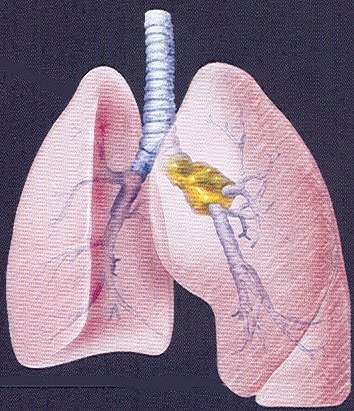

large hilar mass, brochoalveolar #1, brochoalveolar #2, mesothelioma,